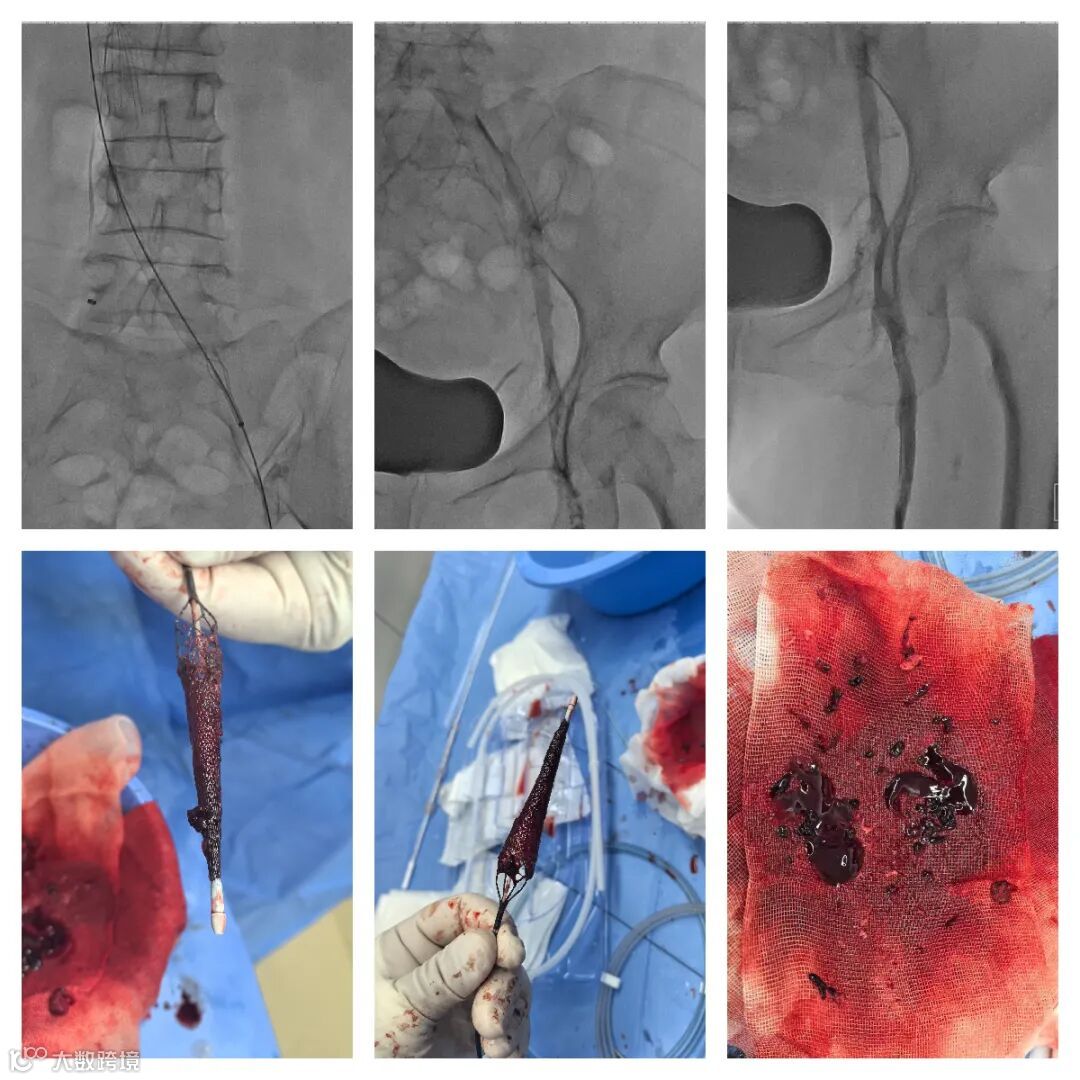

1. 超声引导下穿刺左腘静脉,置入6F鞘管,造影确认。

2. 右股静脉穿刺,造影示:下腔静脉血栓形成。小心通过后放置下腔静脉滤器。

3. 左腘静脉更换Tendfast®14F鞘管,造影示:左下肢全程静脉血栓形成。

4. 送入腾复Tendfast®外周静脉取栓支架,左股静脉拉栓1次,造影显示:左股静脉血流通畅。

5. 左髂静脉血栓负荷较重,通过左髂总静脉后,给予6mm*150mm球囊扩张。

6. 引入Tendfast®外周静脉取栓支架,从左侧髂静脉拉栓2次,造影显示血流恢复通畅。

取出的血栓